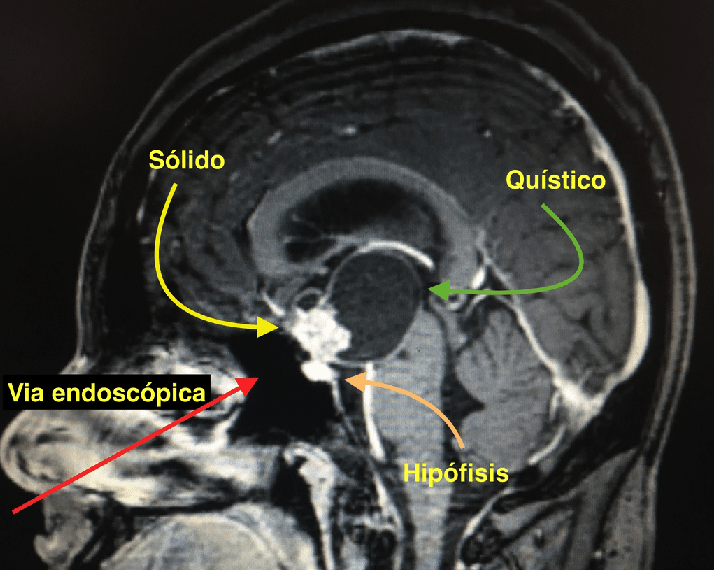

Ver caso clínicoCraneofaringiomas

Los Craneofaringiomas son tumores benignos de la región selar y supraselar derivados de las células epiteliales de la Bolsa de Rathke.